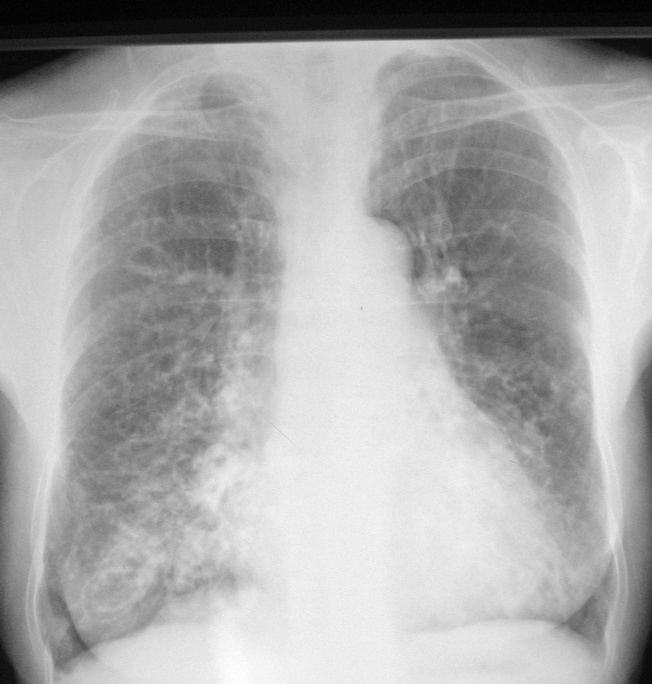

以下是引用拾荒者在2010-9-3 21:20:00的发言:[br]双肺纹理粗乱、模糊,双肺中下野沿纹理示卷发样改变,双侧胸廓饱满,膈肌低平,结合临床考虑:慢支并感染,肺气肿,支扩可能。